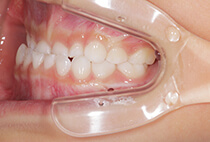

出っ歯を目立たずしっかり治したい。とのご希望、ビジネスシーンでも目立たないインビザラインを選択なさいました。30代男性の症例です。

治療計画は

抜歯した上顎も親知らずまできれいに並べたことで、上下ともに14本ずつ=非抜歯と同じ28本の歯列が完成しました。

治療から2年後も+ホワイトニングできれいな歯並びを保っています。

出っ歯が気になる

上顎前突、過蓋咬合

30代男性

3.5年

唇側矯正、圧下用インプラントアンカー

矯正:1,270,500円+毎月調整量:6,050円

上顎2本抜歯して前歯を下げます。

奥歯のかみ合わせを治します。

インプラントアンカーを使用して前歯をしっかりコントロール、

過蓋咬合(かみ合わせの深さ)を改善しました。